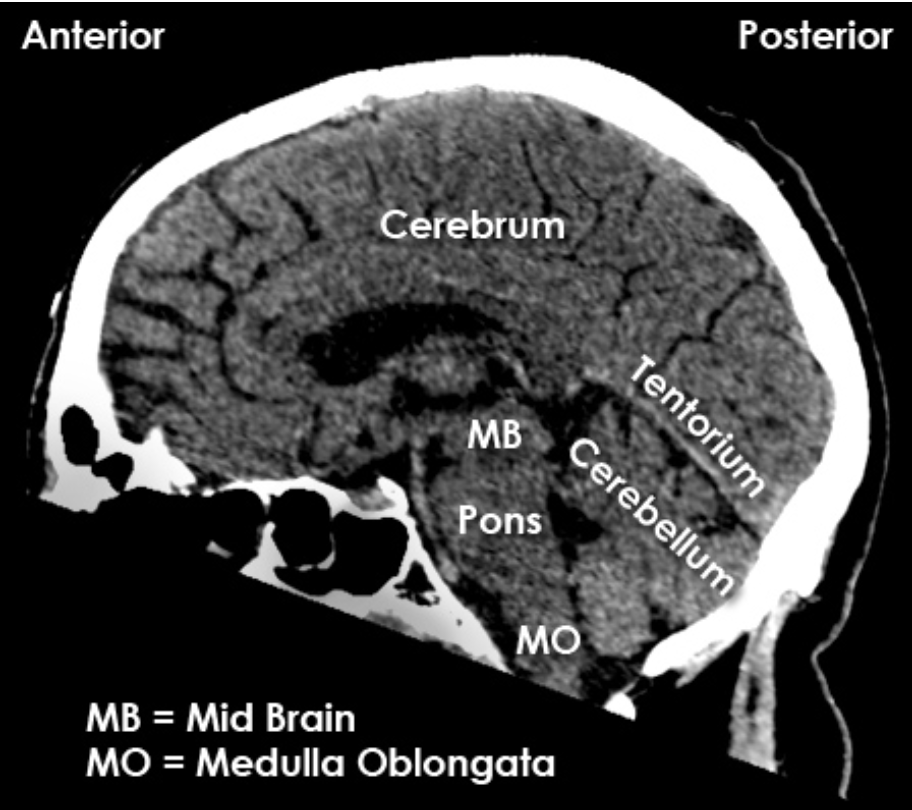

Brainstem